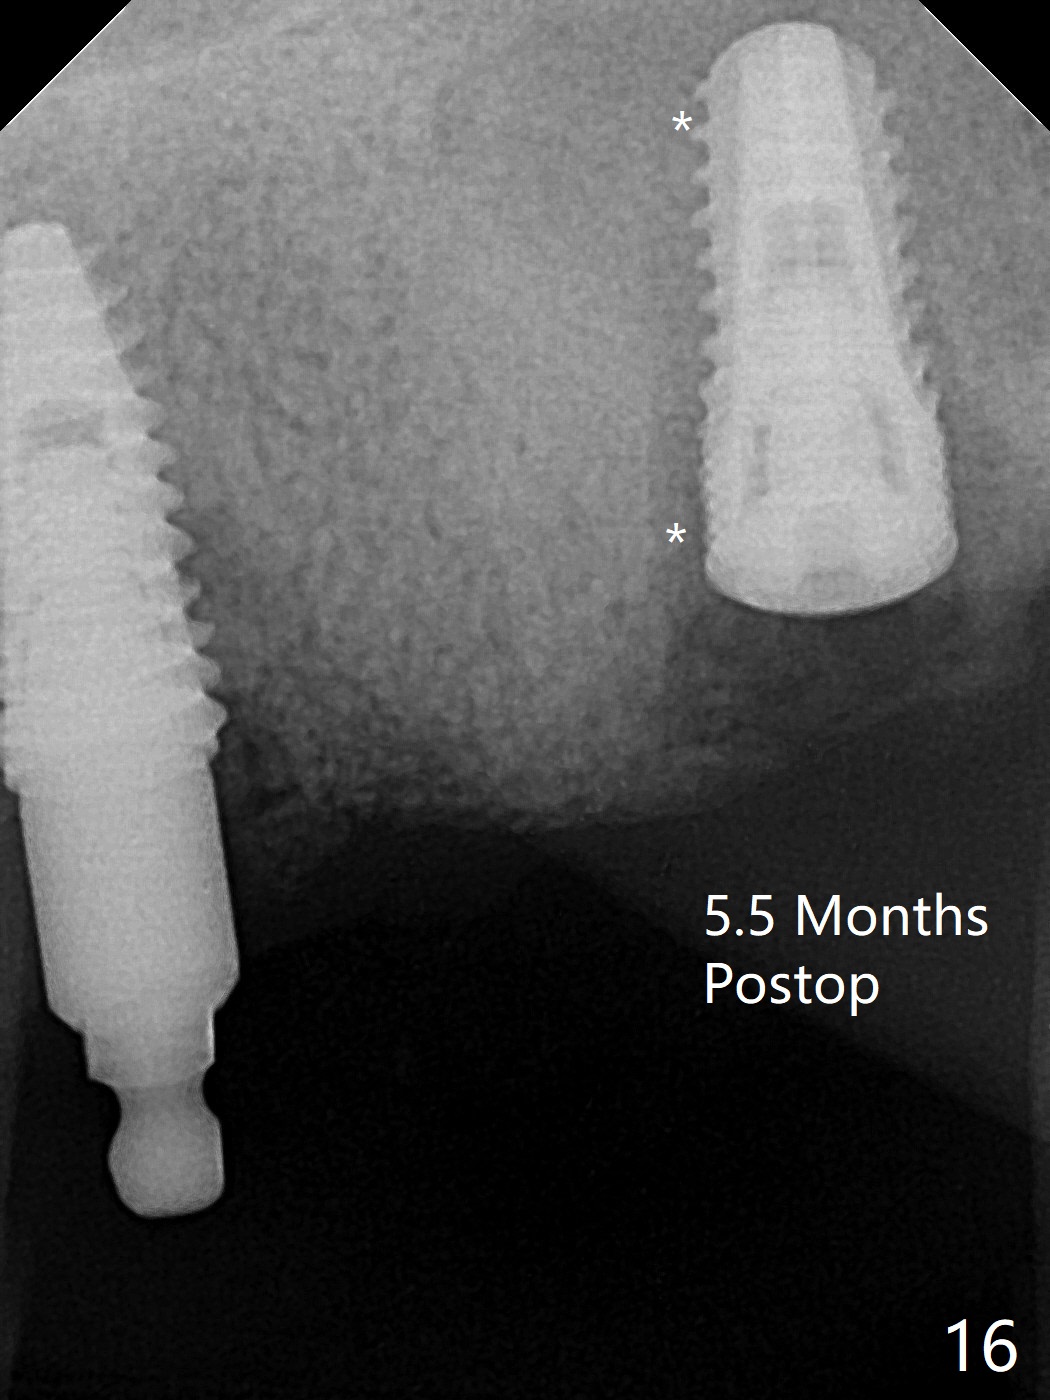

Osteotomy at #13 starts blindly (no incision or tissue punch) with bone expanders. After insertion of parallel pins, intraop CT shows that it is palatal with apparently buccal low bone density (Fig.1); the osteotomy for implant (Fig.2 green) should be shifted buccal and tilted mesial (red, parallel to #11) with incision. In contrast the position, trajectory and depth (Fig.3 <) of the initial osteotomy are acceptable at #11. The implant will be placed as it is (Fig.4). After taking a postop PA (Fig.5), the implant at #11 is placed a little deeper to make sure its slightly subcrestal placement (including distal incision at #11). Following placement of 3.5x4 and 3 mm ball abutments at #11 and 13, cortical allograft with PRF is placed around the implants, especially buccal (Fig.6,7 <). After suturing, the profile of the ball abutments is too low for RPD retention. Due to gravity other than bone density, the number of ball abutments for the maxilla should be more than for the mandible. Soft reline is done to the patient's satisfaction. The retention of the upper RPD after soft reline is satisfactory without pain 7 days postop (Fig.8). The implant at #13 is loose nearly 3 months postop (Fig.9 *: bone loss). The implant is removed while the ball abutment is untightened; the sinus floor is present. It appears that a longer and larger implant is necessary; a 4.5x10 mm dummy implant is unable to be seated deep or achieve primary stability (Fig.10). After sinus lift with 3 mm Bicon osteotome without bone graft, the dummy implant accomplishes the 2 tasks mentioned above (Fig.11). However there is no corresponding definitive implant in stock. Implant system needs to be changed; with a change in implant driver, the depth control is lost. The final implant is placed deep (Fig.12). With back up, stability is lessened; a healing screw is placed; with collagen plug, the wound is sutured (Fig.13). The wound heals 1 week postop (Fig.15). The RPD is soft relined. Retention from the ball abutment at #11 is apparently critical. The RPD and #11 implants (4 months postop) are stable, while the wound at #13 heals 1.5 months postop (Fig.15). There is space around the implant 5.5 months postop (Fig.16 *). The 5x10mm SM implant is found to be loose upon uncover and removed. After debridement, 5.3x8 mm SM and 5.5x9 mm IBS dummy implants are inserted without stability, while 6x9 mm definitive one with stability (Fig.17). Cortical allograft is placed in deficiency areas (*). The osteotomy has no roof (sinus floor), but the sinus membrane is intact. Small amount of bone graft (Fig.18 *) is placed before implantation. There appears to be bone around the new implant (Fig.19 (3D sagittal section) *).